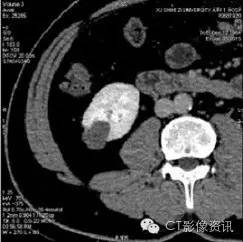

下图是横轴位5mm平扫及三期强化图像,参与病例讨论的医生半数以上认为有强化。

病灶是肯定的,讨论的焦点是有无强化,这是判断病灶性质的关键。

薄层图像三期观察,半数以上医生坚持有强化。初步诊断良性实质性占位。